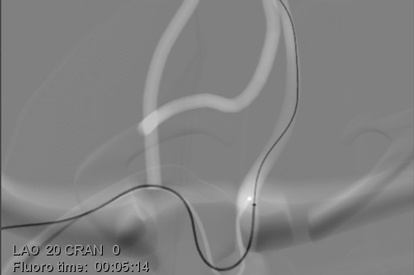

The ANGIO Mentor simulator is an essential tool for clinicians to practice and acquire the skills needed for performing endovascular interventions. Trusted by medical associations, hospitals, training centers, and the medical device industry globally, it provides trainees with realistic clinical settings to practice endovascular interventions using fluoroscopic and ultrasound guidance.

Offers true-to-life simulation of the clinical environment, including advanced imaging modalities like fluoroscopy/echocardiography, hemodynamic monitoring, medications, and interventional devices

C-arm Basic Skills Module

Endovascular Basic Skills Module